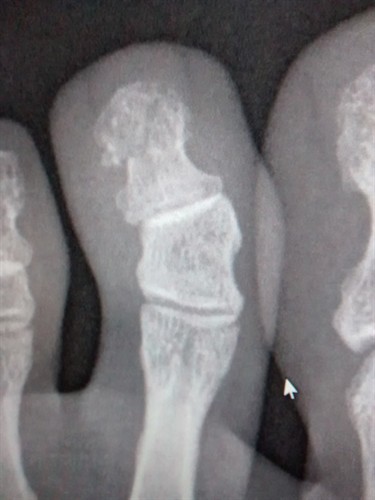

On day 7, I was still limping and I told my chiropractic intern at the clinic what had happened and she suggested we take an X-ray. All students at NUHS, no matter what program they’re in, are able to receive free chiropractic, naturopathic, and acupuncture care at the Whole Health Center. Sure enough, the X-ray showed a fracture just under the nail bed. Everyone involved in my care was surprised that my nail didn’t fall off. Although there’s no way to prove it, I bet it’s because of all the natural treatments I was doing!